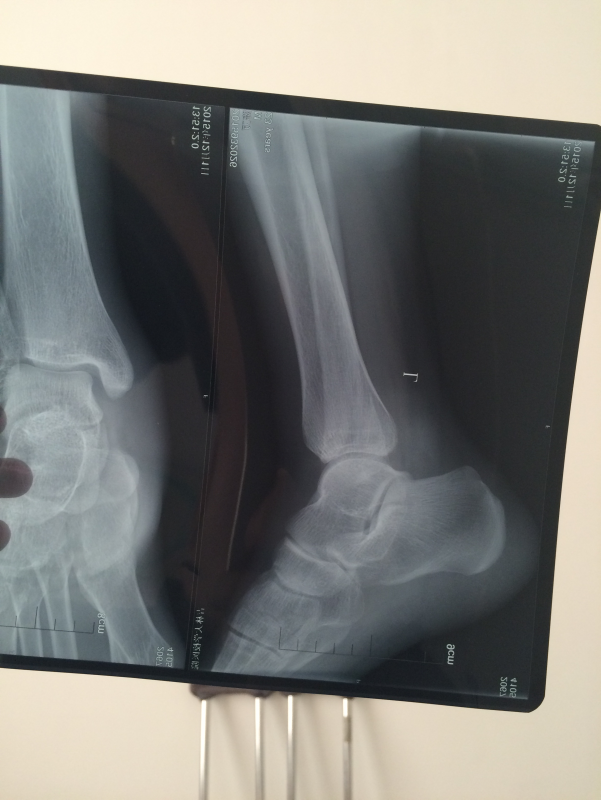

左脚踝腓骨骨折 已有10人参与

需要打钢板吗? 发自小木虫IOS客户端 |